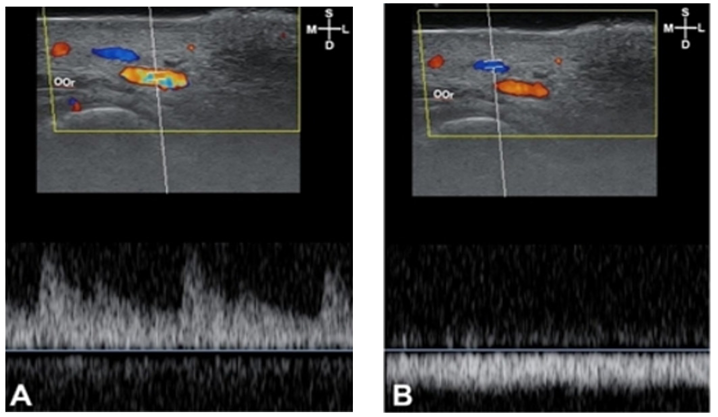

Doppler function of ultrasound devices has color doppler and power doppler pulse and is useful to observe the blood vessel condition. Doppler effect refers to a phenomenon in which the frequency of a sound wave reflected from a moving tissue is changed when a sound wave originating from a transducer returns from approaching red blood cell, the increased frequency indicates that bloodstream is coming toward the transducer, is recognized as positive, and is depicted as color red-yellow <Fig. 1>. When the reflected frequency from departing red blood cell comes in, the bloodstream is recognized as negative and is depicted as color blue <Fig. 2>.

Fig. 1. Bloodstream sonography of F4: pumping bloodstream image (A) indicates arterial flow. Flowing bloodstream image (B) indicates the venous flow. S: superficial; D: deep; M: medial; L: lateral